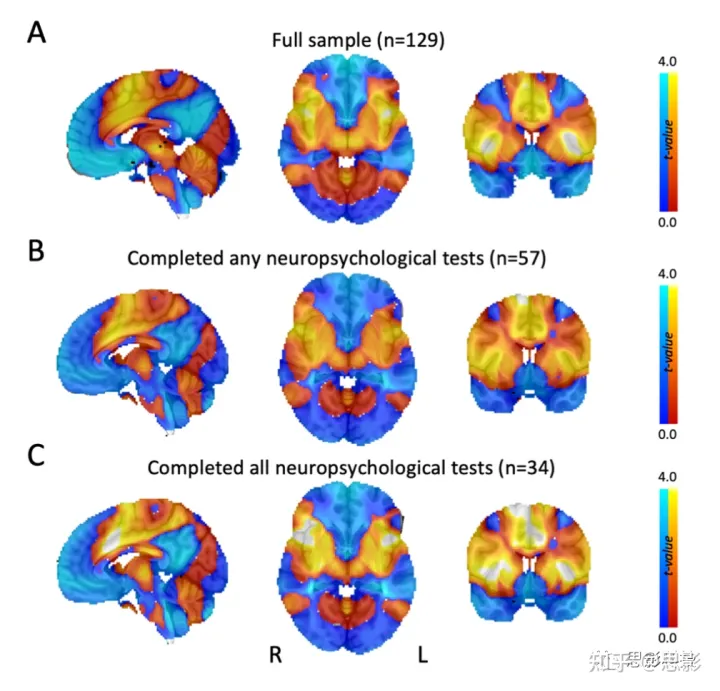

在接受神经心理学测试的患者子集中,戒烟的患者和未戒烟的患者在智商、执行功能、工作记忆、语言理解、情绪或社交内向方面没有显著差异。仅从这部分患者计算的成瘾缓解图与使用完整数据集生成的图几乎相同(补充材料图 9)。

图 S9:具有神经心理学评估的子样本代表了完整样本。

当将分析限制在接受任一(B)或所有(C)神经心理学评估的患者时,我们的主要分析(A)的成瘾缓解网络图保持不变。地图未设置阈值以方便比较。